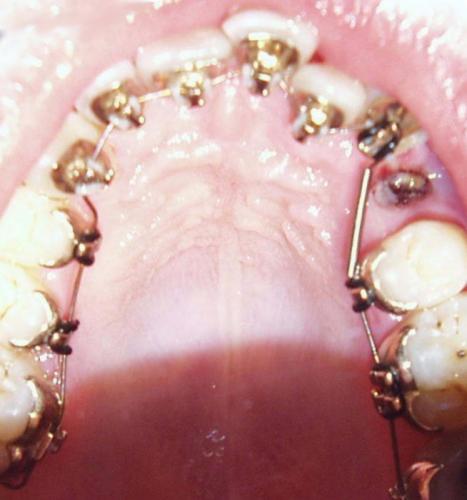

Während der Behandlung

Bild 1: Einsetzen der Lingualapparatur; der kleine Backenzahn ist bereits entfernt.

Bild 2: Der Zahnbogen ist schon weiter ausgeformt, die Miniimplantate sind plaziert und der Lückenschluß wird eingeleitet.

Bild 3: Der Unterkiefer wird erst mit zeiticher Verzögerung mit einbezogen, da die Behandlungsaufabe dort überschaubarer ist.